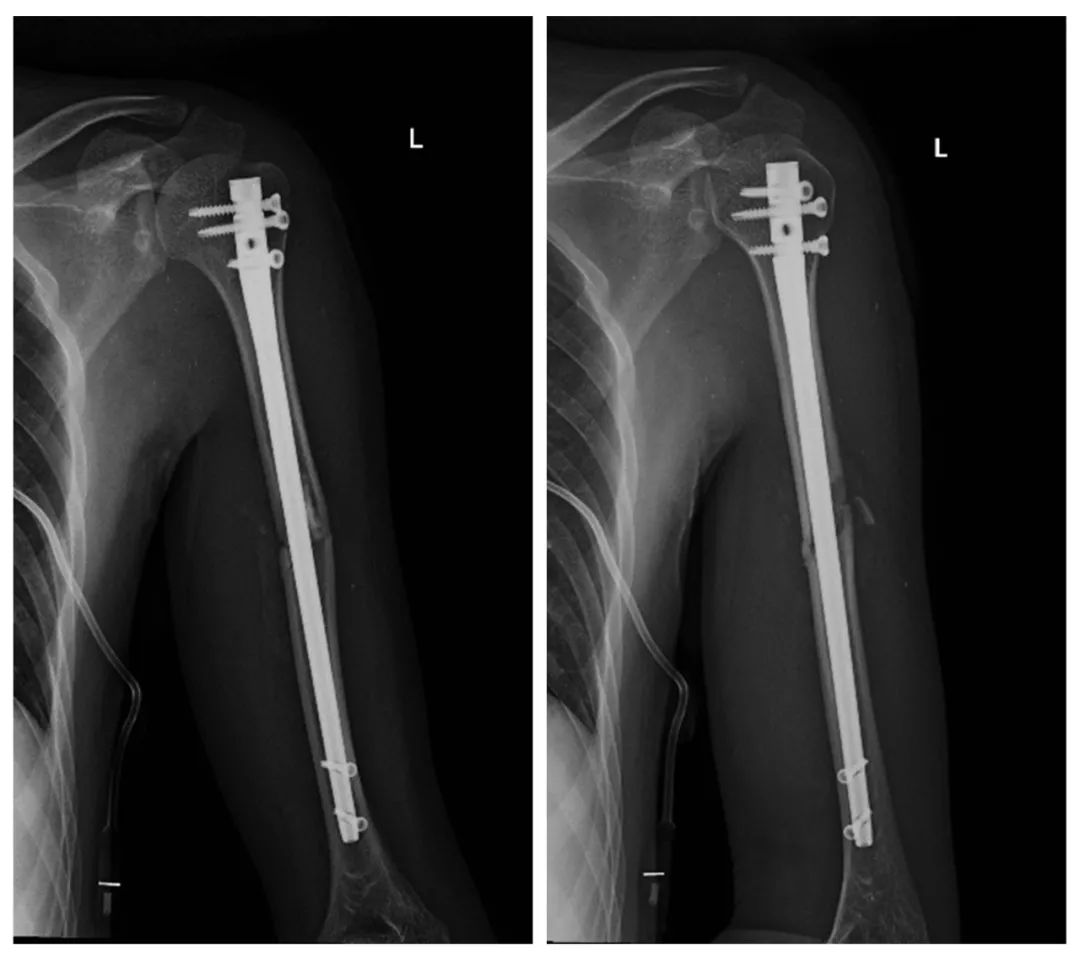

本次手术在术前利用“临床影像工作站”读取患者术前的CT影像数据,运用人工智能算法对骨折部位进行精准分割和重建,高效实施术前规划,术中利用光学导航系统精确制导,实现肱骨干骨折全息可视化复位、髓内钉精准定位。整台手术共耗时45 分钟,完全省去传统手术中采用C形臂透视辅助复位和置钉的过程。术后X线显示骨折端获得解剖复位,术后肢体活动良好。

术后X线片